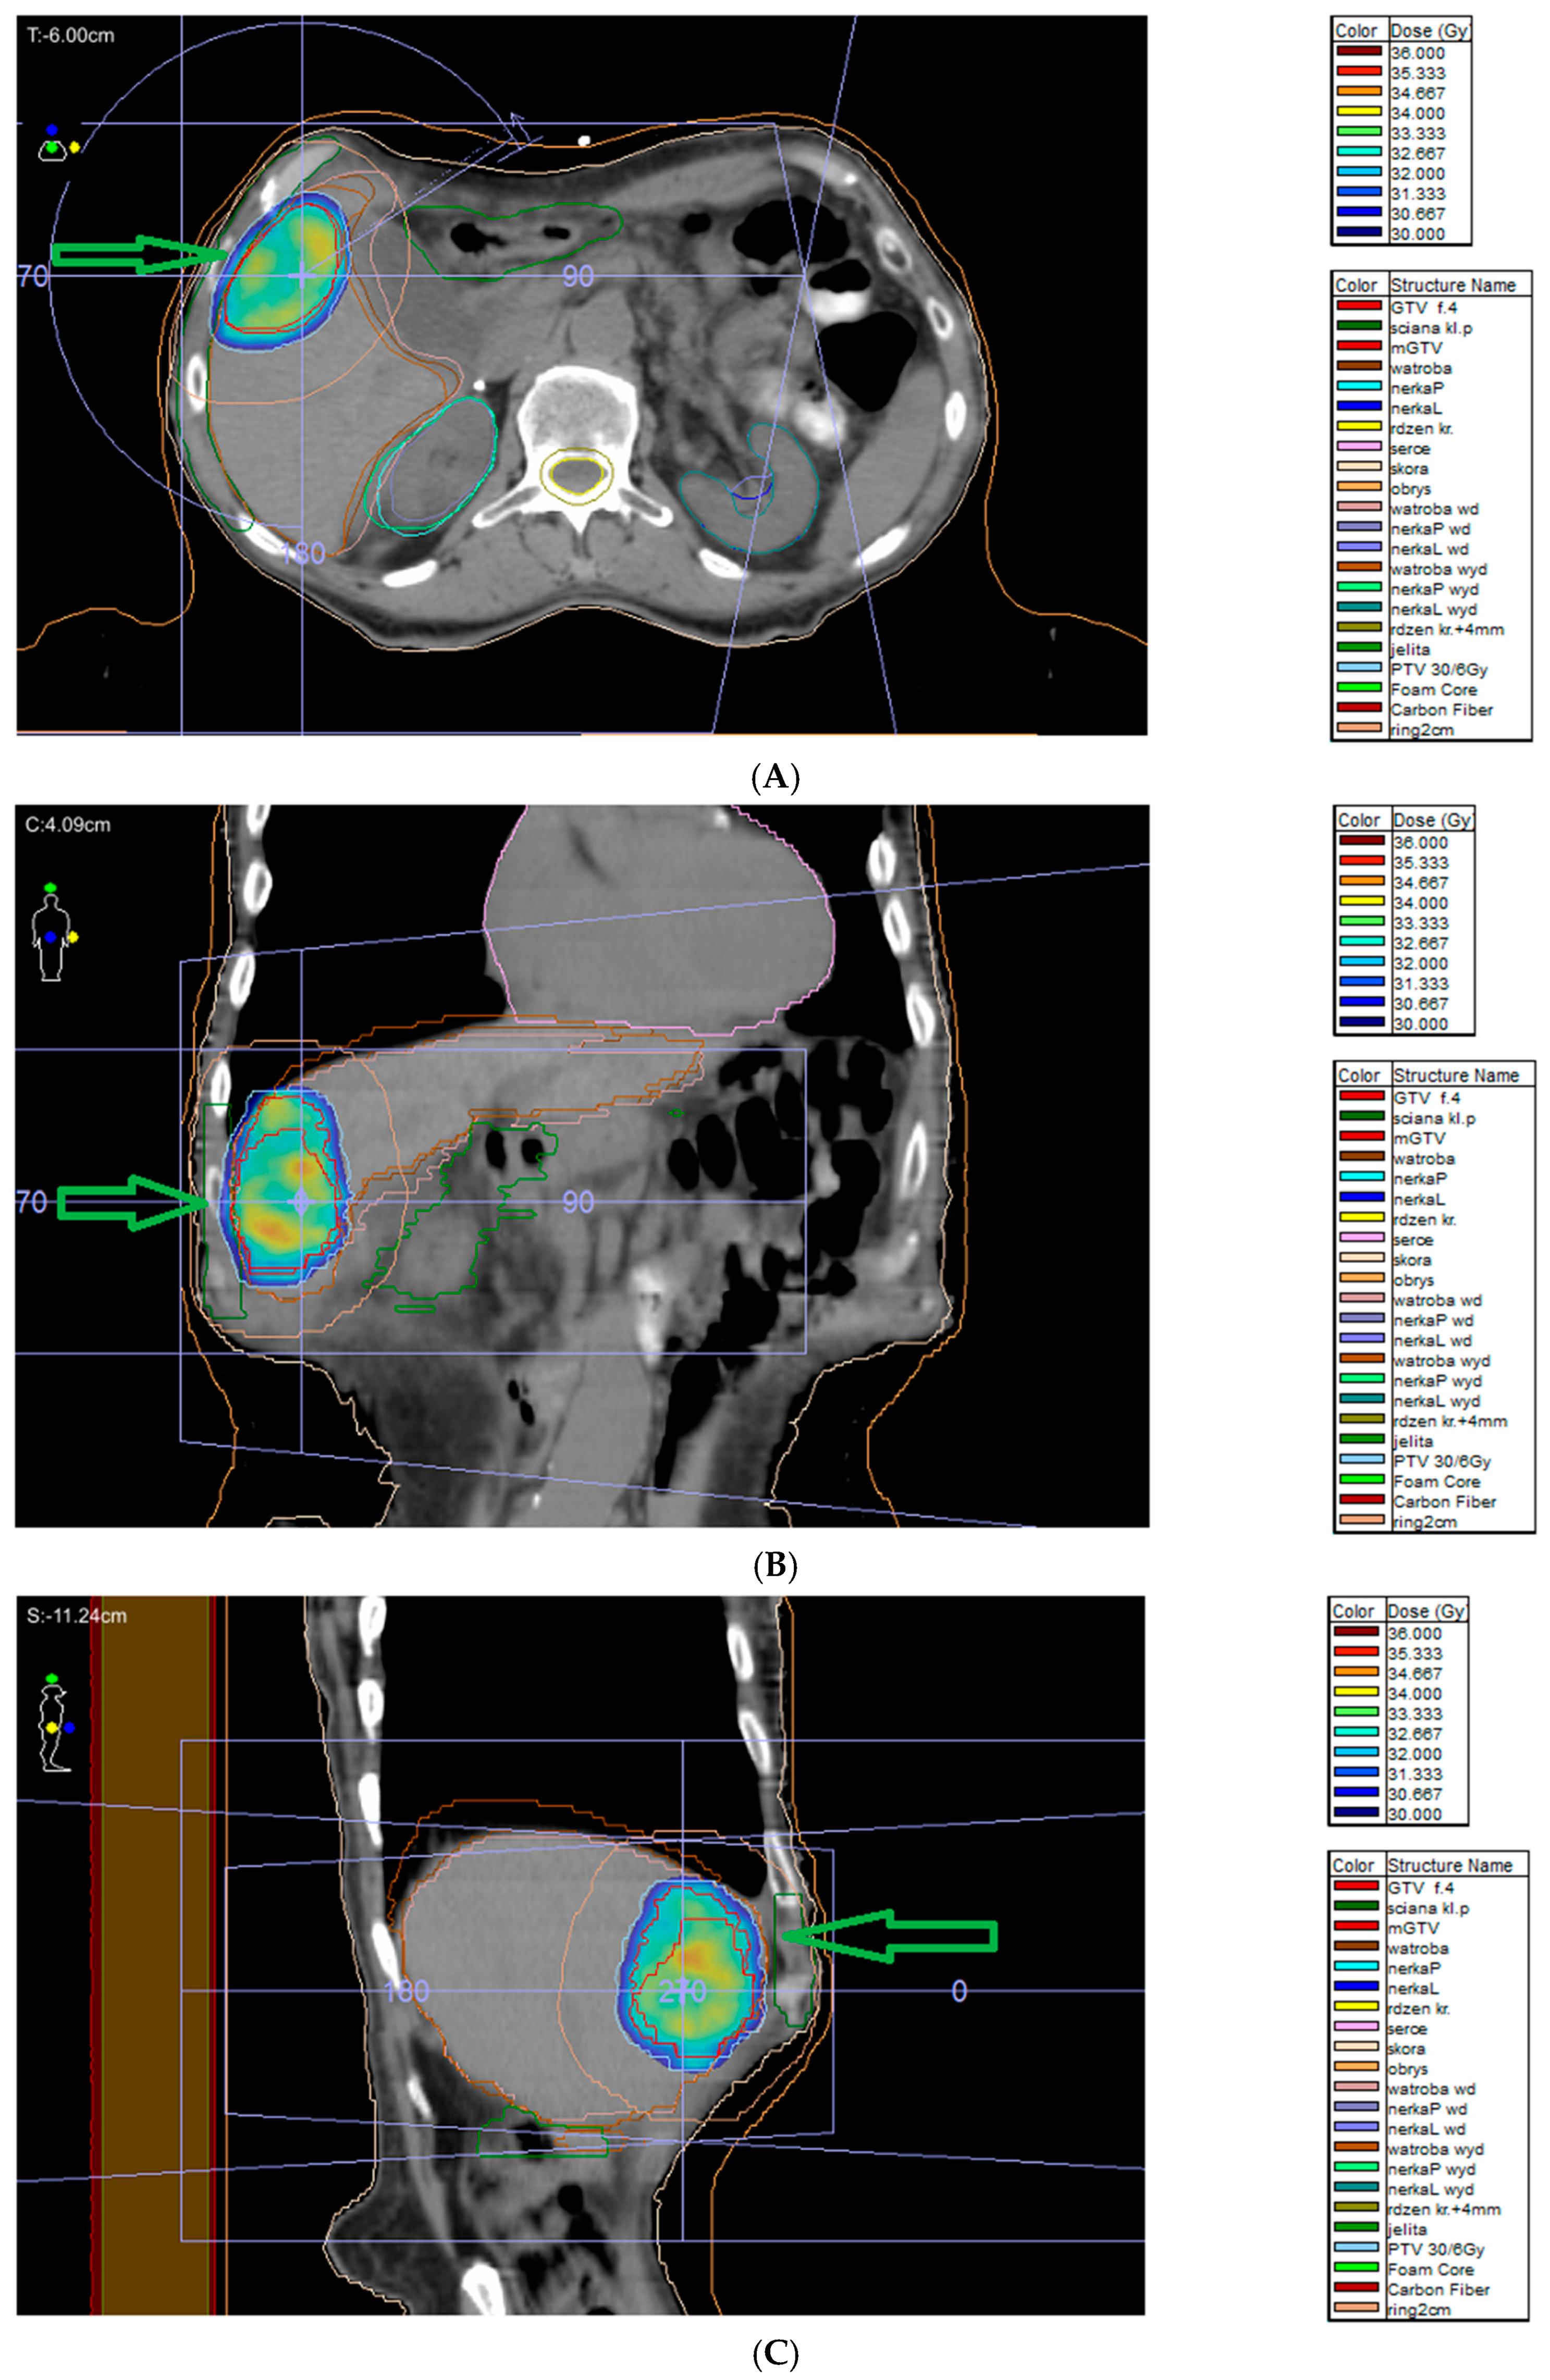

7.9. External Beam Radiotherapy (ERBT) and Hypofractionated Stereotactic Radiotherapy (hSRT)